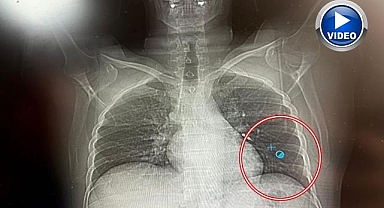

İmplant vidası ciğerine kaçan hasta ölümden döndü